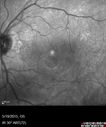

This has been a bad 3 months. Last month was the worst. When he first had cataract surgery after both were done, he was doing pretty well. He could read the paper. Then all of a sudden a fog would go past his eyes. Had ECCE OU about 6 months ago. VA OD: sc20/50 PHNI NscJ10 VA OS: sc20/63+1 PHNI NscJ10 Swelling did not respond to drops but did to a posterior subtenon kenalog injection

Pseudophakic Cystoid Macular Edema Both Eyes411 views81 year old man with vision loss about 4 months following ECCE. Did not respond to topical therapy but did fine with PST kenalog00000